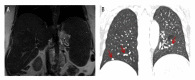

BACKGROUND Sarcoidosis is a systemic disease that can affect any organ, including the liver. It is manifested by the presence of non-caseating granulomas within involved organs, most commonly the pulmonary, lymphatic, and hepatic system. Unlike pulmonary or lymphatic involvement, hepatic involvement is usually asymptomatic and it is underdiagnosed. Here, we report a case of a patient with a history of pulmonary sarcoidosis who developed hepatic sarcoidosis. CASE REPORT 68-year-old female with pulmonary sarcoidosis with a 2-week history of severe abdominal pain and epigastric tenderness presented to our center. Abdominal magnetic resonance imaging (MRI) demonstrated mild hepatic fibrosis and cirrhosis. A thorough workup was performed including a liver biopsy which showed chronic non-necrotizing granulomas consistent with sarcoidosis. She was started on prednisone and subsequently improved. The patient was symptom-free on follow-up 1 month later. CONCLUSIONS The majority of patients with hepatic sarcoidosis are usually asymptomatic, with only 5-30% presenting with abdominal pain, jaundice, nausea, vomiting, and hepatosplenomegaly. In rare cases, hepatic sarcoidosis can lead to cholestasis, portal hypertension, cirrhosis, or Budd-Chiari syndrome. Treatment with steroids is the mainstay of therapy; however, in severe cases, patients may require liver transplantation. This case report demonstrates that hepatic sarcoidosis is a serious condition, and if not treated, can lead to portal hypertension and cirrhosis. In patients with sarcoidosis, early detection and longitudinal follow-up is important in preventing overt liver failure.

Figures